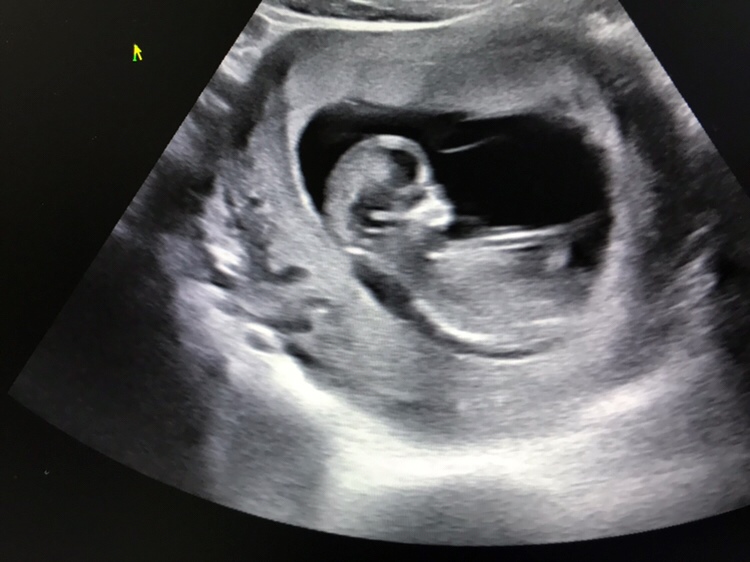

孕16周+4天

B超是要看屁股部位有没有小🐔,这个图片看不到屁股!

心率很高,男宝宝概率比较大